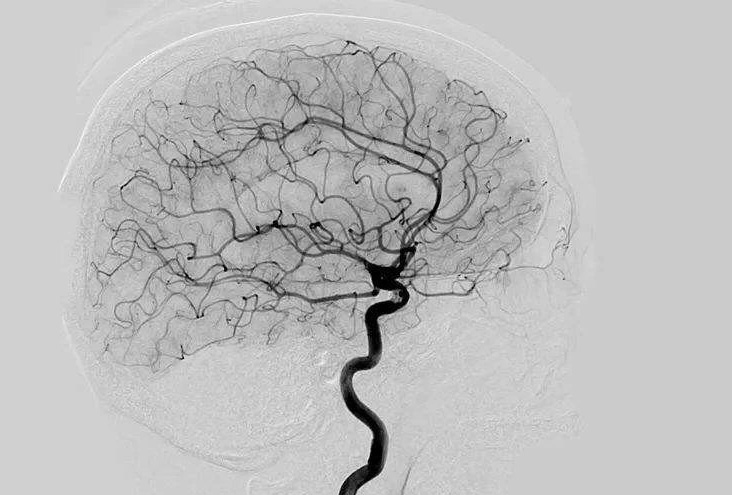

Digital Subtraction Angiography 血管造影機(jī)又稱數(shù)字減影血管造影機(jī),是通過(guò)電子計(jì)算機(jī)進(jìn)行輔助成像的血管造影方法,應(yīng)用計(jì)算機(jī)程序進(jìn)行兩次成像完成的。在注人造影劑之前,第一次成像工作,圖像轉(zhuǎn)成數(shù)字信號(hào)儲(chǔ)存,注人造影劑后,再次成像并轉(zhuǎn)換成數(shù)字信號(hào),兩次數(shù)字相減,消除相同的信號(hào),得到只有造影劑的血管圖像。臨床主要應(yīng)用于冠心病、心律失常、瓣膜病和先天性心臟病的診斷和治療。